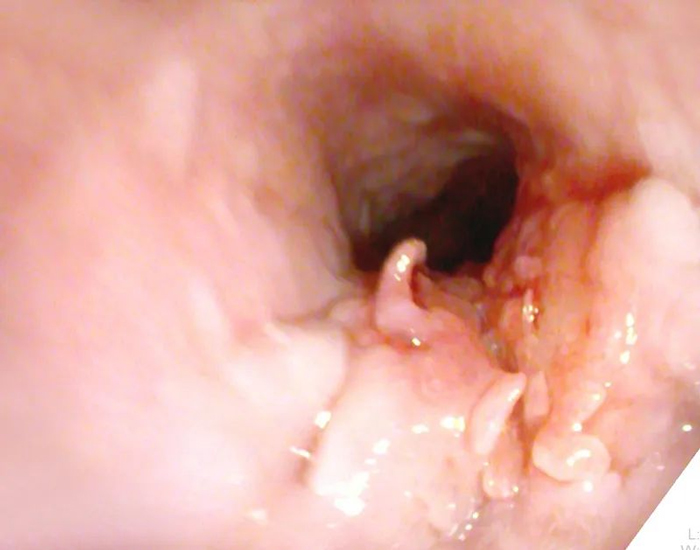

發(fā)現(xiàn)食管中段

開出“菜花”樣腫物

腫瘤科段朋飛醫(yī)師:食管粘膜光滑,“菜花”樣的東西消失不見了。